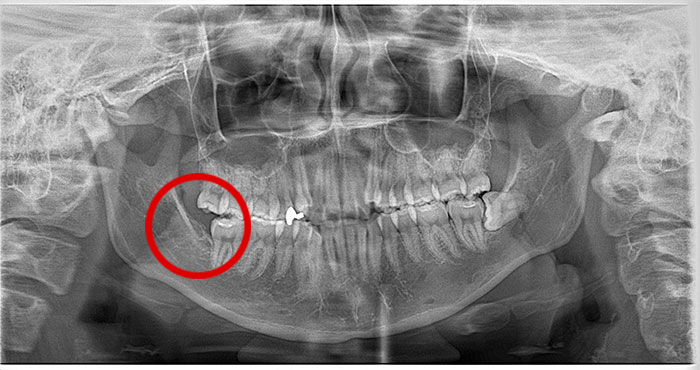

Before

After

真横になった親知らずを抜歯したレントゲン写真です。